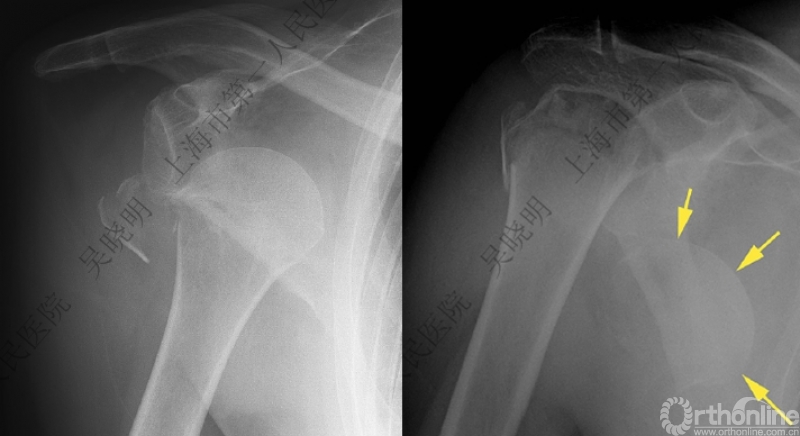

特别警惕伴肱骨头外翻合并大结节骨折的肩关节脱位

警惕:有无肱骨头外翻

肩关节前脱位伴大结节骨折:颈干角正常

无肱骨头外翻伴大结节骨折的老年性肩关节前脱位

Neer 分型:二部分大结节骨折脱位:手法复位

伴大结节骨折的老年性肩关节前脱位伴肱骨头外翻

肩关节前脱位合并大结节骨折&肱骨头外翻:外翻压缩型(Neer 分型)

对这型骨折进行手法复位会导致肱骨头和肱骨干之间的连续性消失。肱骨头和肱骨干之间连续性尚存,肱骨头前脱位(Robsion 3b)